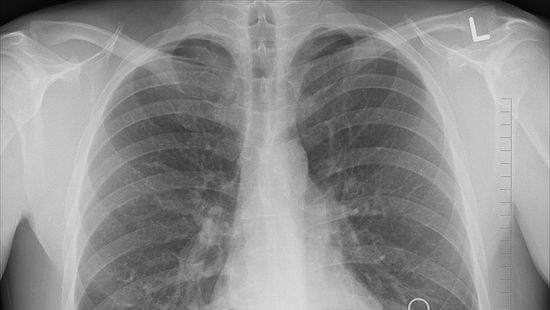

INSIDER 2021. 10. 29. Elképesztő bizonyíték: Aki be van oltva, annak nem károsodik a tüdeje Jelentős a különbség az oltott és oltatlan betegek tüdőkárosodása tekintetében koronavírus-fertőzés esetén.